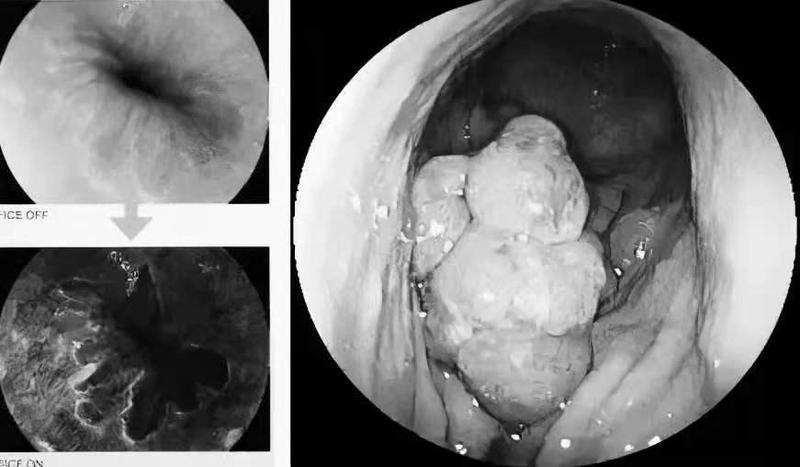

肠镜检査就是通过肛门插入一根软管,通过软管前端的“摄像头"査看整个大肠的技术。

通常肠镜内部还有可以放置操作器械的通道,从而能够在肠镜下钳取组织做病理检查,甚至进行切除病变等操作。

约95%的肠癌是肠息肉演变而来的,肠镜可以轻易发现息肉,并能顺便切除,就从根本上杜绝了肠癌的发生。

肠镜进入肠道后,能清晰地观察整个肠道內壁小到1-2mm的东西,像小米那么大的也能看得见。

如果肠镜发现了息肉,医生可能在检查过程中就把息肉切除了。如果息肉很大,或者发现肿瘤等其他可疑病变,医生会做活检,取部分或全部病变组织送去化验,病理科大概5-7个工作日后会发出检查报告,告诉我们病变是什么,是良性的还是恶性的,是癌还是癌前病变。